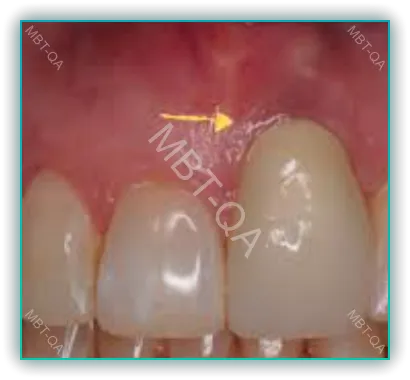

2. 임플란트 주변 잇몸의 색 변화

임플란트 주변 잇몸의 색 변화는 임플란트 시술 후 흔히 발생하는 문제 중 하나입니다. 이러한 색 변화는 임플란트의 금속 부분이 잇몸을 통해 비쳐 보이기 때문에 발생합니다. 특히, 잇몸이 얇거나 연한 색을 가진 사람들에게서 더 자주 발견됩니다.

또 다른 해결책은 잇몸 이식 수술입니다. 잇몸이 얇은 경우, 잇몸 조직을 추가하여 두께를 증가시킬 수 있습니다. 이 방법은 잇몸의 건강을 증진시키고, 임플란트 주변의 색 변화를 감소시키는 데 효과적입니다.

- 잇몸 이식 또는 조절: 잇몸의 색상 변화나 모양 문제에 대해 잇몸 이식 수술이나 조절을 통해 개선할 수 있습니다. 이는 임플란트 주변 잇몸의 건강과 외관을 향상시킵니다.